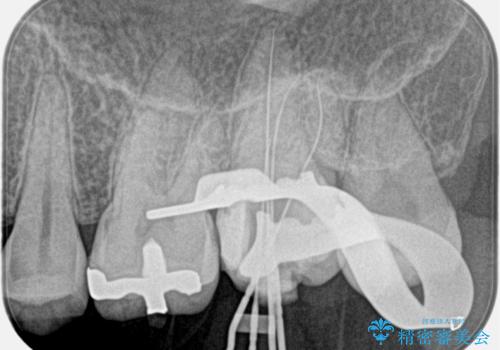

- 奥歯がズキズキ痛いことを主訴に来院されました。

治療にて歯髄は保存できないと判断したため、根管治療を行いセラミッククラウンにて修復しております。

自発痛の既往がある場合は、抜髄の適応となることが多いです。